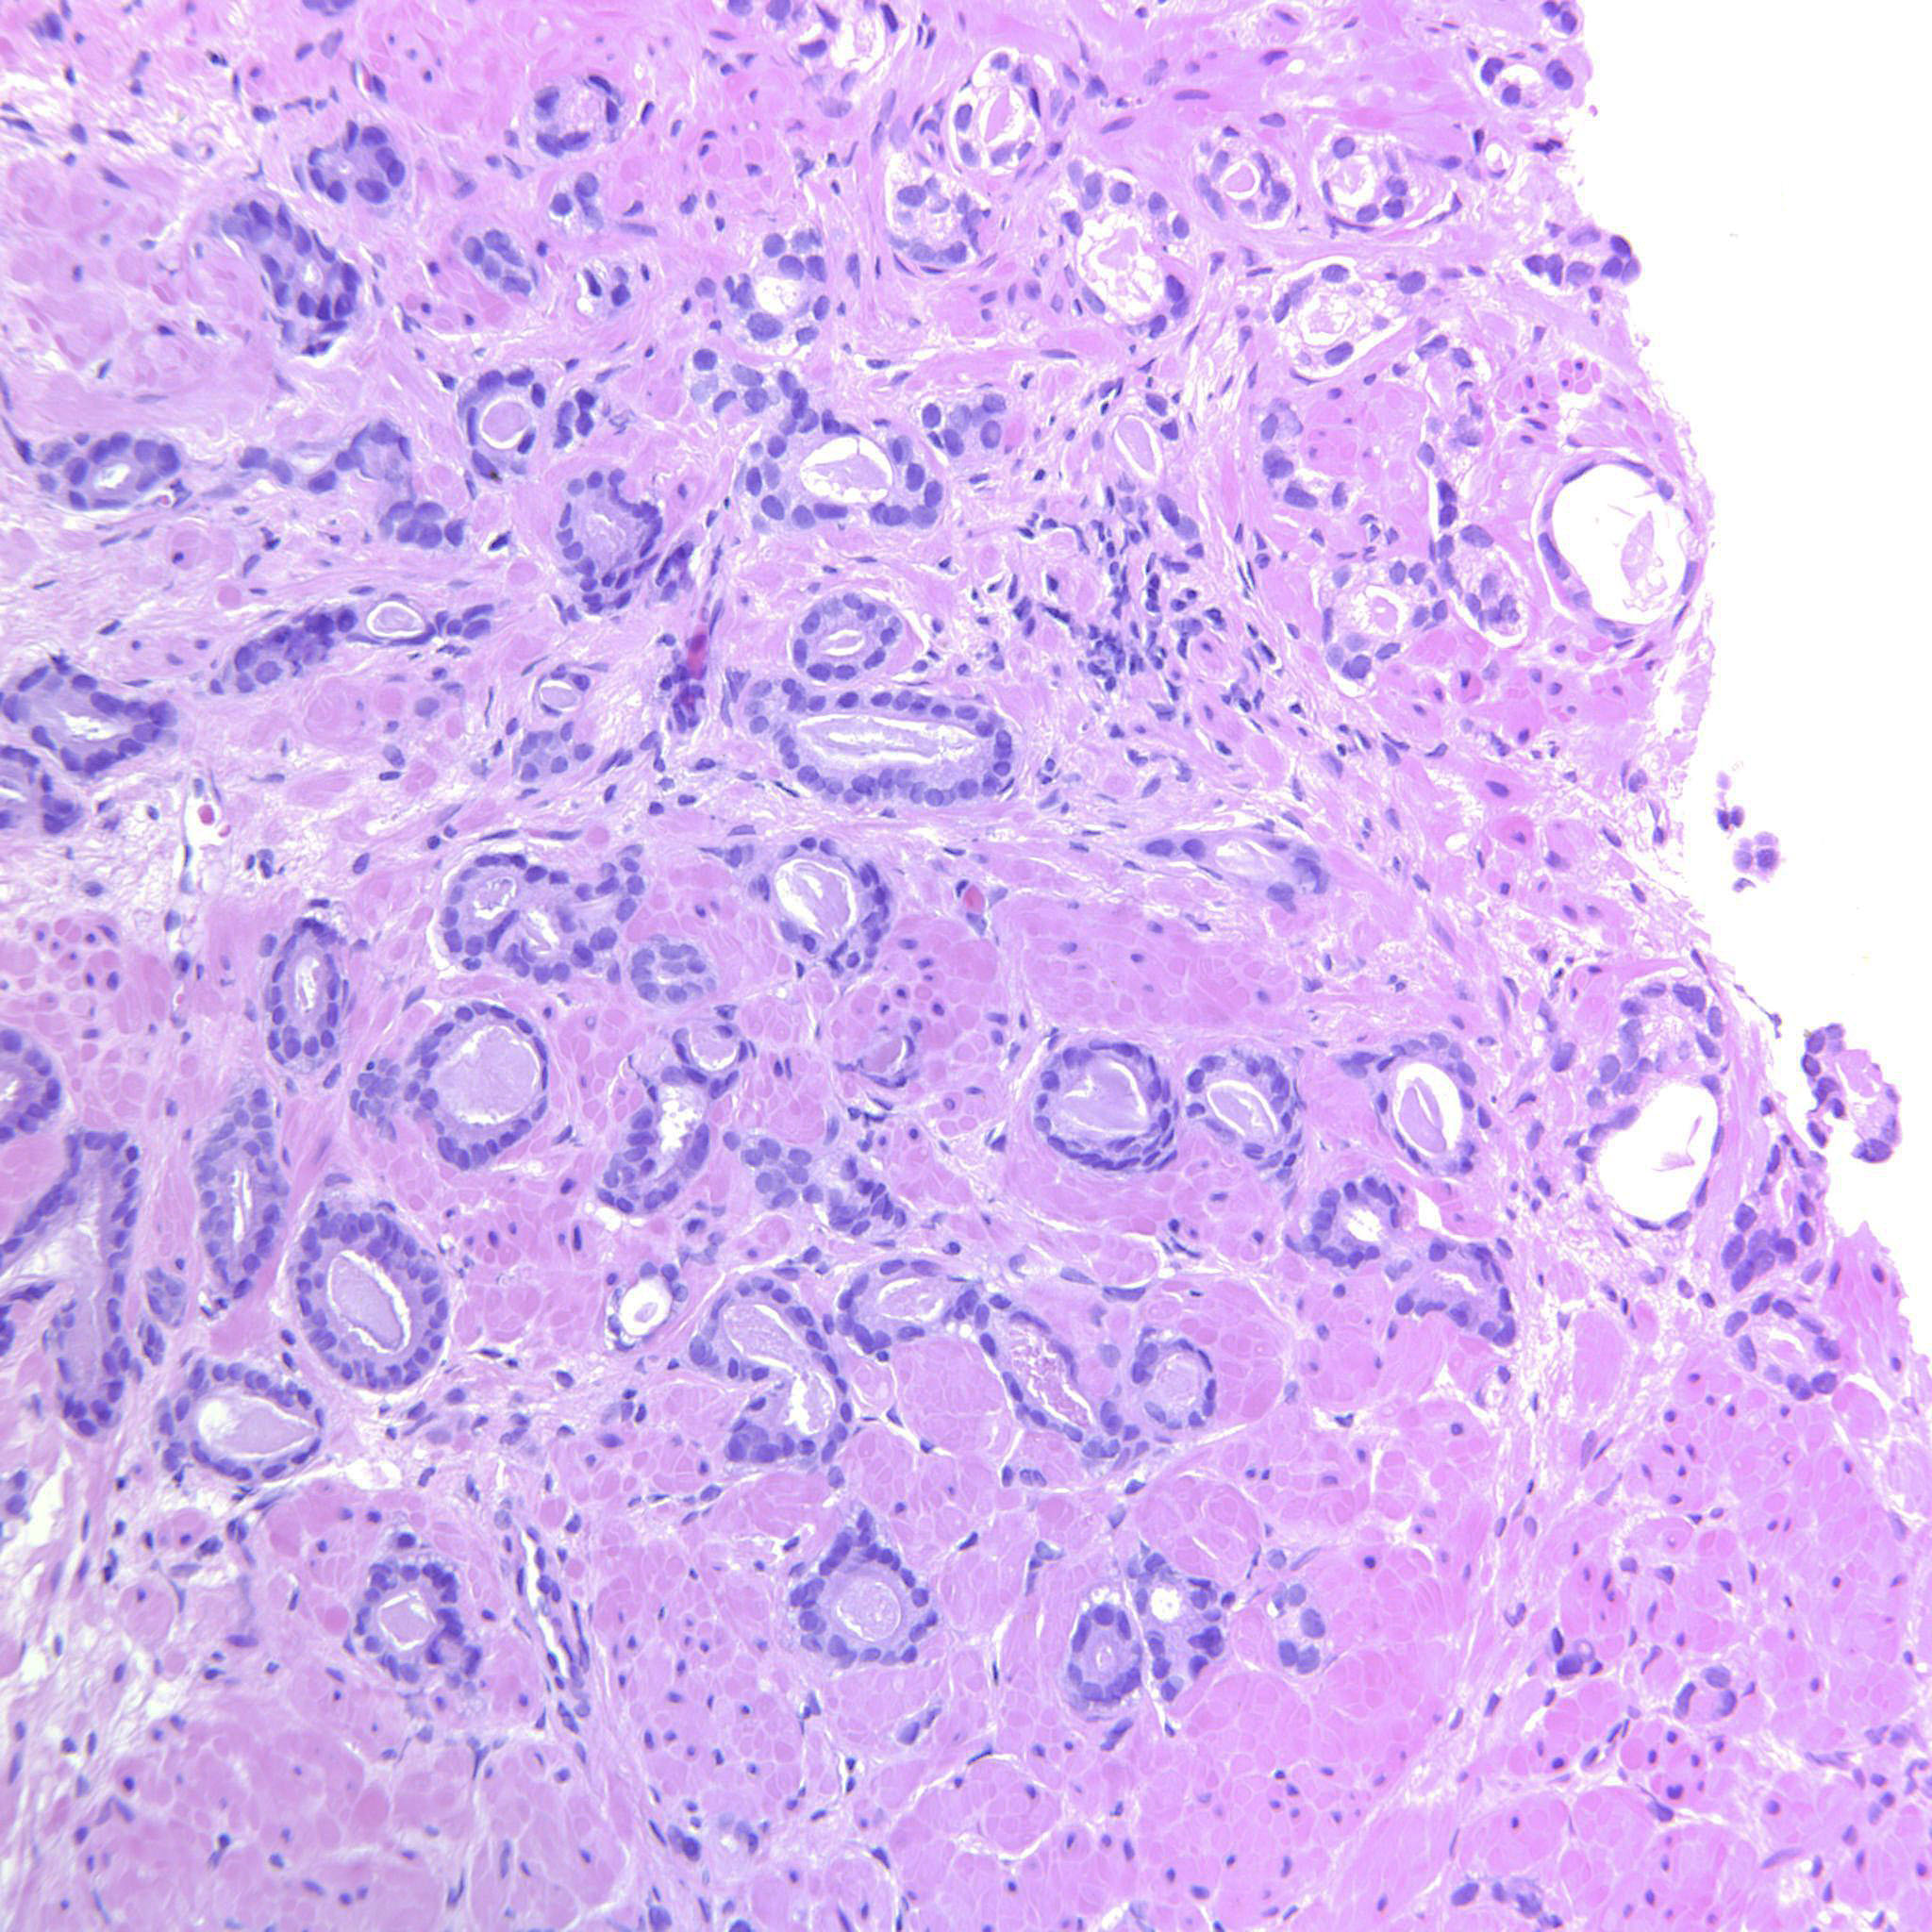

Consensus grade: GS 3+3=6 (ISUP 1)

Case description (by case creator):

Circumscribed cancer glands. Occasional seemingly solid strips of epithelium that may be tangential cuts.